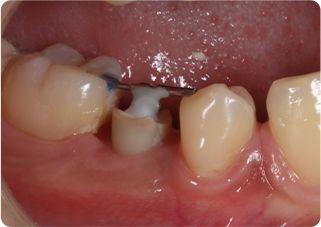

精密根管治療③

術前

術後

| 主訴 | 奥歯で噛むと痛い |

| 治療期間/回数 | 1ヵ月、4回 |

| 価格(税込) | 88,000円(税込) |

| リスク・副作用 | 病変再発、歯根破折の可能性 |

| ポイント | う蝕検知液を用い、むし歯の取り残しが無いようにし、ラバーダム防湿を行い、無菌的に根管治療を行った。根管充填材は、殺菌作用の強い保険適応外のMTAセメントを使用した。 |